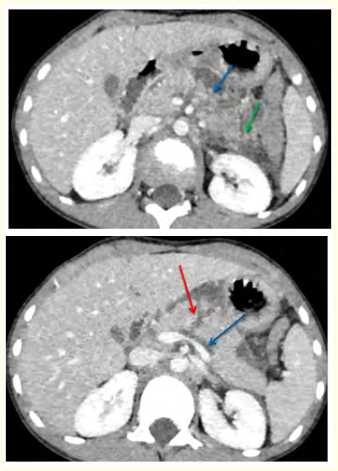

Firm Pancreatic Trauma in Children: About a Case

Nourrelhouda Bahlouli, Fatima Chait, Khadija Laasri, Nazik Allali, Siham El Haddad and Latifa Chat. 12(12): 01-05.